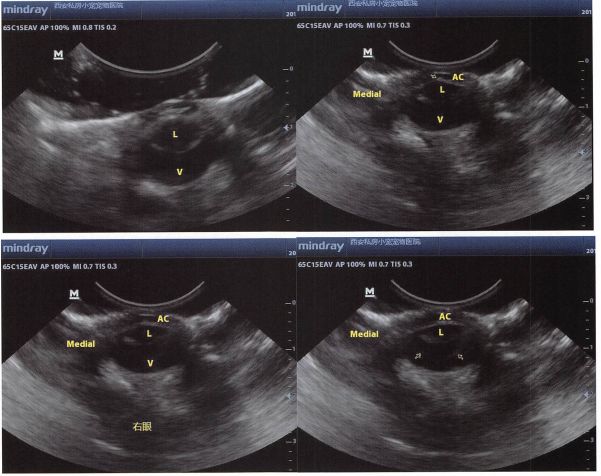

6.增距垫

距离探头太近的地方,可能看不清,所以一些浅表的器官或组织,需要增距。可以购买专业的增距装备,价格比较高。也可自制,用避孕套装水,不能有气泡。用旧的医用橡胶手套也可以自制增距垫。公犬的两个睾丸可相互为增距垫。

使用保鲜膜做增距垫也是一个简单实用的方法:找一块保鲜膜拉展,挤上较多的耦合剂(耦合剂内不能有气泡),然后用这个保鲜膜包着耦合剂包住探头,用胶布固定牢固,就可以使用了。尤其是可用于眼科超声。